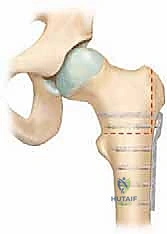

الهدف الأسمى في هذه الحالات المعقدة هو إجراء تدخل جراحي لإنقاذ المفصل يُعرف بـ قطع العظم الانثنائي بين المدورين (Flexion Intertrochanteric Osteotomy). هذه الجراحة الاستباقية والمتقدمة لا تكتفي بتثبيت العظم، بل تعيد هندسة المفصل بالكامل. تهدف الجراحة إلى استعادة التوازن الميكانيكي الطبيعي بين رأس وعنق عظم الفخذ، وإعادة توجيه الجزء العلوي من عظم الفخذ في الفضاء ثلاثي الأبعاد، مما يلغي الاحتكاك المدمر ويعيد للمفصل انسيابيته.

الجراحة المتقدمة: قطع العظم الانثنائي بين المدورين (Imhäuser Osteotomy) بالتفصيل

نصل الآن إلى جوهر هذا الدليل الطبي. جراحة قطع العظم الانثنائي بين المدورين هي عمل فني هندسي حيوي. الهدف منها ليس إعادة رأس الفخذ المنزلق إلى مكانه (لأن محاولة إرجاعه بالقوة قد تقطع الأوعية الدموية وتسبب نخر العظم AVN)، بل الهدف هو تغيير زاوية عنق وعظم الفخذ السفلي ليتناسب مع الوضع الجديد لرأس الفخذ، وبالتالي القضاء على التشوه الميكانيكي.

الخطوة الثالثة: قطع العظم (The Osteotomy)

باستخدام مناشير جراحية دقيقة، يتم إجراء قطع (إزالة إسفين عظمي - Wedge Resection) في عظم الفخذ في منطقة بين المدورين. حجم وشكل هذا الإسفين العظمي هو ما يحدد مقدار التصحيح.

الخطوة الرابعة: التدوير والتصحيح (Correction and Rotation)

بمجرد قطع العظم، يتم تدوير الجزء السفلي من عظم الفخذ (الساق) للأمام وللداخل ليصطف بشكل مثالي مع الجزء العلوي (الرأس والعنق). في هذه اللحظة، يختفي "تشوه قبضة المسدس" وتستعاد ديناميكية المفصل الطبيعية.